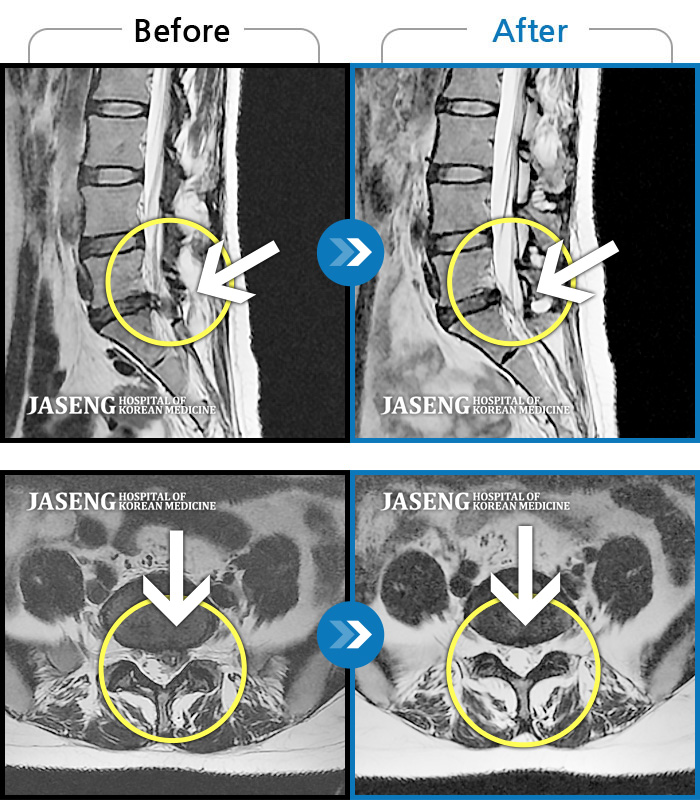

Before

After

환자에게 사전 동의를 받아 동일 조건에서 촬영되었습니다.

개인에 따라 치료 후 부작용이 발생할 수 있으니 의료진과 상담 후 치료를 진행하시기 바랍니다.

오른쪽 허리 통증, 허리를 숙일 때 다리 당김 증상

허리 골반 통증, 앉을 때 우측 다리 당김 및 저린 증상